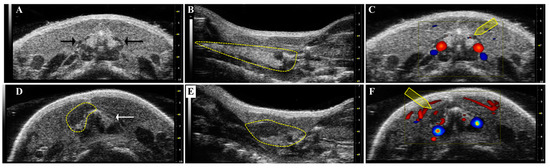

- Mancini, M.; Vergara, E.; Salvatore, G.; Greco, A.; Troncone, G.; Affuso, A.; Liuzzi, R.; Salerno, P.; Scotto di Santolo, M.; Santoro, M.; et al. Morphological ultrasound microimaging of thyroid in living mice. Endocrinology 2009, 150, 4810–4815. [Google Scholar] [CrossRef] [PubMed]

- Lavarello, R.J.; Ridgway, W.R.; Sarwate, S.S.; Oelze, M.L. Characterization of thyroid cancer in mouse models using high-frequency quantitative ultrasound techniques. Ultrasound Med. Biol. 2013, 39, 2333–2341. [Google Scholar] [CrossRef] [PubMed]

- Mancini, M.; Greco, A.; Salvatore, G.; Liuzzi, R.; Di Maro, G.; Vergara, E.; Chiappetta, G.; Pasquinelli, R.; Brunetti, A.; Salvatore, M. Imaging of thyroid tumor angiogenesis with microbubbles targeted to vascular endothelial growth factor receptor type 2 in mice. BMC Med. Imaging 2013, 13. [Google Scholar] [CrossRef] [PubMed]

| HFUS | Transgenic Tg-TRK-T1 | PTC | Tumor growth | [59] | |

| HFUS | Transgenic Rb+/− Transgenic BRAF-TRβPV/PV | MTC PTC FTC | Tumor growth | [60] | |

| HFUS | antiVEGFR2-MB | Transgenic Tg-TRK-T1 | PTC | VEGFR2 | [61] |

| HFUS | FTC-133—Orthotopic | FTC | Orthotopic implantation | [34] | |